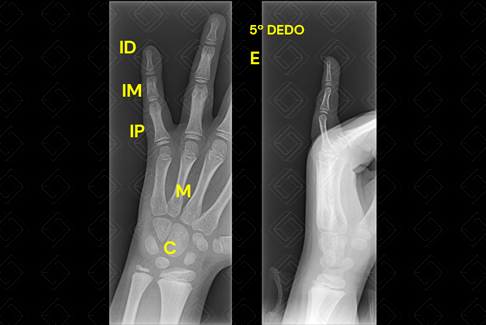

Texto alternativo para a imagem Radiografia do quinto dedo da mão esquerda, projeções PA e perfil. Créditos: Athena Hub/Medical Harbour

Legenda das siglas: C = carpo; [cms-watermark] ID = interfalangeana distal; IM = interfalangeana média; IP = interfalangeana proximal; M = metacarpo.

As radiografias de dedos devem ser obtidas em posteroanterior ( PA) , oblíquo e perfil da região de interesse.